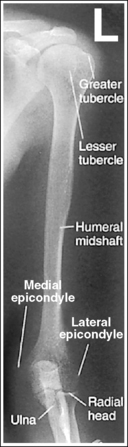

The humerus is in an AP projection. The medial and lateral humeral epicondyles are demonstrated in profile, and the radial head and tuberosity are superimposed over the lateral aspect of the proximal ulna by approximately 0.25 inch (0.6 cm). The greater tubercle is demonstrated in profile laterally, the humeral head is demonstrated medially in profile, and the vertical cortical margin of the lesser tubercle is visible approximately halfway between the greater tubercle and the humeral head.

• An AP projection is obtained by placing the patient in a supine or upright AP projection, with the affected arm extended. Supinate the hand and externally rotate the elbow until an imaginary line drawn between the palpable humeral epicondyles is aligned parallel with the IR (Figure 4-88). This positioning places the proximal radius anterior to the ulna, causing the radial head and tuberosity to be superimposed over the lateral ulna by approximately 0.25 inch (0.6 cm), and places the greater tuberosity in profile.

• Detecting humeral rotation. Rotation of the humerus is a result of poor humeral epicondyle positioning. When the humeral epicondyles and the greater tuberosity are not demonstrated in profile, measure the amount of radial head and tuberosity superimposition of the ulna to determine how the patient should be repositioned. If less than 0.25 inch (0.6 cm) of the radial head and tuberosity are superimposed over the ulna, the elbow and humerus have been excessively externally rotated (see Image 100). If more than 0.25 inch (0.6 cm) of the radial head and tubercle are superimposed over the ulna, the elbow and humerus have been internally rotated (see Image 101).